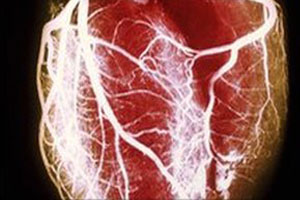

The majority of people who experience an OHCA event do not receive bystander-assisted cardiopulmonary resuscitation or other timely interventions that improve the likelihood of survival to hospital discharge.